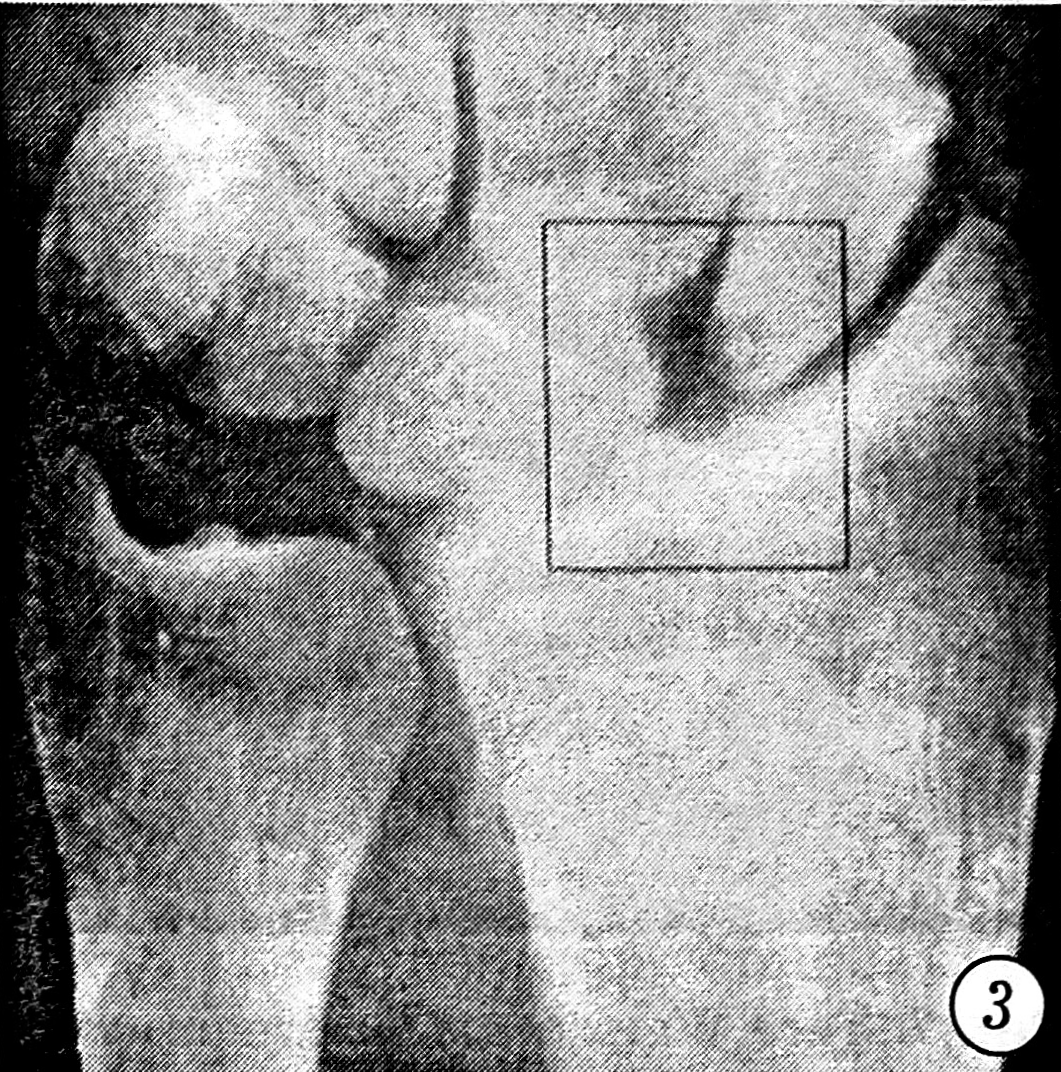

Исследовались первичные рентгенограммы и контрольные, сделанные после выполнения репозиции. Отбирались те случаи, в которых хотя бы на одном снимке присутствовали один или несколько из следующих рентгенологических признаков повреждения межзапястных связок: увеличение полулунно-ладьевидного угла более чем до 70° (рис. 1), симптом «кольца» дистального полюса ладьевидной кости (рис. 2), изменение формы и расширение полулунно-ладьевидного промежутка до 3 мм и более (рис. 3), нарушение непрерывности трех «запястных арок» (рис. 4), расширение полулунно-трехгранного промежутка (рис. 5) и увеличение полулунно-головчатого угла более чем до 20° (рис. 6) [5]. Результаты исследования представлены в табл. 1.

Рис. 3. Расширение до 3 мм и более и изменение формы полулунно-ладьевидного промежутка.